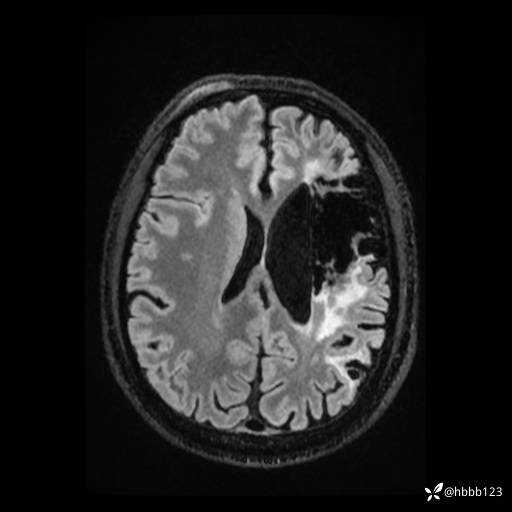

T2: